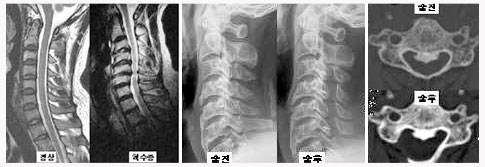

척추관 협착증의 방사선 소견